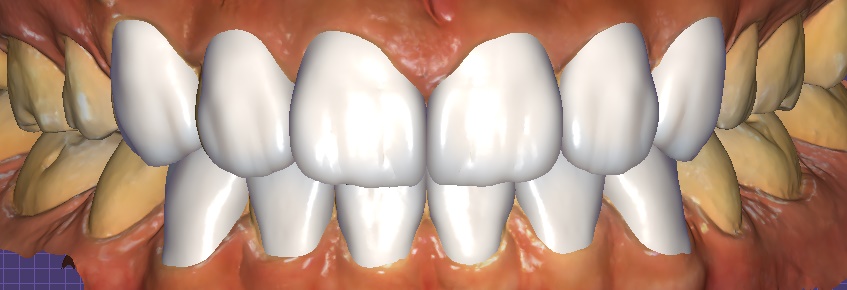

① Digital scan & design

– Precise data acquisition with an intraoral scanner → 3D design and simulation

Object Zero laminate simulation